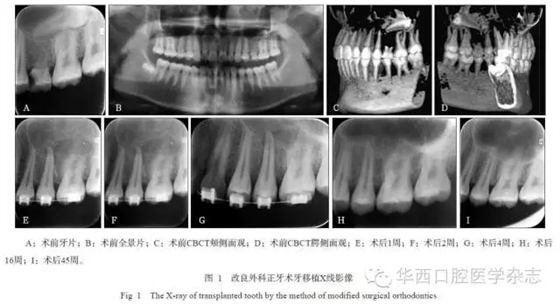

牙移植術(shù)后,均采用正畸片段弓或正畸弓絲黏接固定4~6周,術(shù)后定期隨訪6個月以上,觀察移植牙愈合狀況及X線影像改變。在術(shù)后2~12周,根據(jù)牙周愈合狀況、牙冠色澤的變化、電活力測試與X線根尖區(qū)影像等綜合評估,酌情判斷是否進(jìn)行根管治療。

45例移植牙經(jīng)過手術(shù)異位移植、正畸固定4~6周后,逐漸獲得穩(wěn)固,并行使咀嚼功能。經(jīng)0.5~2年的隨訪觀察,34例移植牙均未出現(xiàn)牙根吸收、牙齒松動等并發(fā)癥,達(dá)到成功標(biāo)準(zhǔn);11例移植牙中存在松動小于Ⅱ度、移植牙類牙周膜影增寬、牙槽骨楔形吸收、牙根吸收(但小于等于2.0?mm)等一項(xiàng)或幾項(xiàng)情況,能承擔(dān)部分咀嚼功能,達(dá)到有效標(biāo)準(zhǔn)。隨訪期內(nèi)未見失敗拔牙病例。

2組移植牙術(shù)后6個月的臨床和影像結(jié)果見表1和2。統(tǒng)計分析表明:1)A、B組的松動度、根管治療比率有統(tǒng)計學(xué)差異(P=0.021, P=0.025),而牙冠色澤變化、電活力測定無統(tǒng)計學(xué)差異(P=0.225, P>0.05)。2)A、B組的移植牙根吸收、牙槽骨吸收有統(tǒng)計學(xué)差異(P=0.025,P=0.038),而牙周膜影像改變無統(tǒng)計學(xué)差異(P=0.169)(表2)。A組療效優(yōu)于B組。